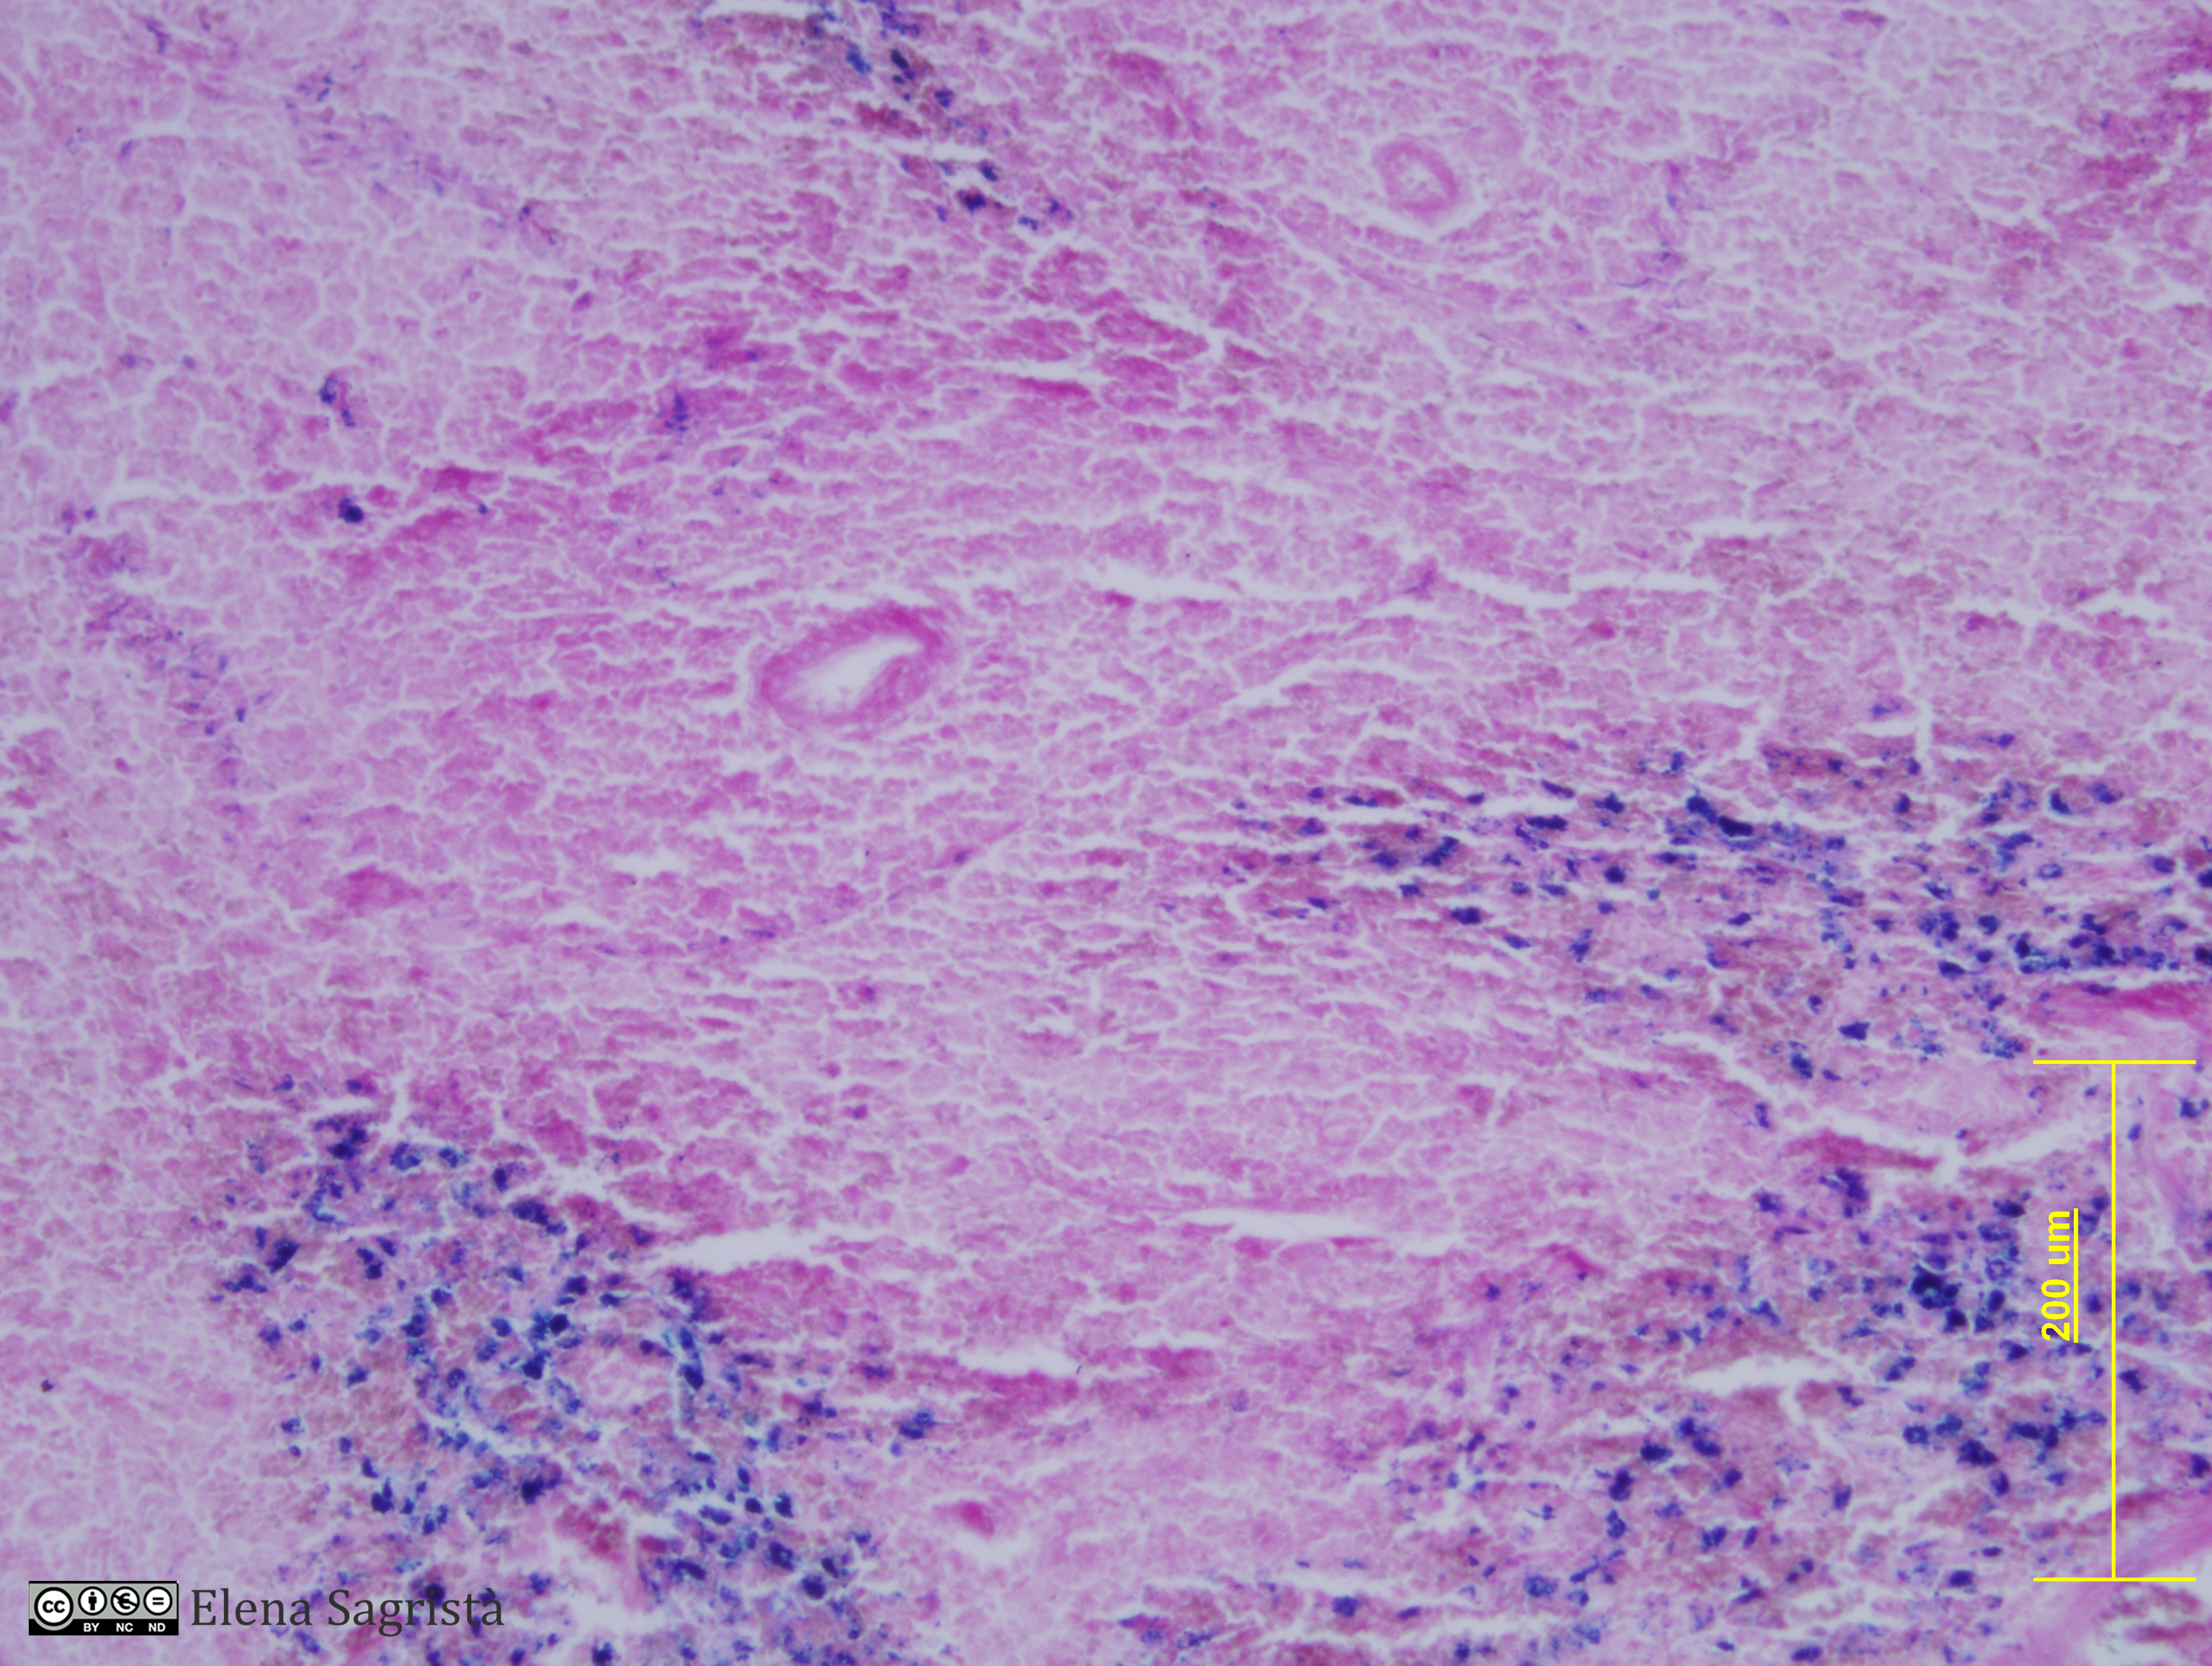

Histologia imatges: 23 Sang, Melsa, Tim i Vas limfàtic

Imatges de preparacions histològiques de Sang, Melsa, Tim i Vas limfàtic. Microscòpia òptica.

SAGRISTÀ I MATEO, Elena, Universitat de Barcelona. Departament de Biologia Cel·lular. Histologia imatges: 23 Sang, Melsa, Tim i Vas limfàtic. [consulta: 6 de maig de 2026]. [Disponible a: https://hdl.handle.net/2445/61480]